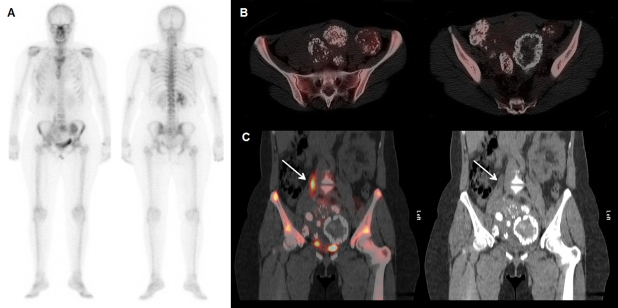

Presentamos el caso de una mujer de 53 años con carcinoma ductal infiltrante de mama derecha de 2,7 cm, grado III y N+ (3/18 ganglios linfáticos axilares), pT2N1, intervenida de manera conservadora, que completa el tratamiento mediante quimioterapia (ciclofosfamida-epirubicina-5-fluorouracilo) y taxol, sumado a radioterapia y hormonoterapia. Para el estudio de extensión lesional acude al servicio de medicina nuclear donde se realiza una gammagrafía ósea tras la inyección intravenosa de 740 MBq de 99mTc-hidroxi-difosfonato y la obtención de imágenes planares de cuerpo completo en proyección anterior y posterior (fig. 1A), observándose varios focos de hipercaptación del trazador localizados en la zona pelviana. A fin de caracterizar las lesiones apreciadas y su localización anatómica, se realiza un estudio SPECT/CT de pelvis (fig. 1B), donde se continúan evidenciando varios focos de captación aumentada intrapélvicos en relación con una miomatosis calcificada, sin que se evidencien depósitos patológicos sugestivos de malignidad a nivel óseo. Posteriormente se realiza una tomografía computarizada de tórax y abdomen con contraste intravenoso, donde se aprecia un útero aumentado de tamaño por la existencia de varios miomas calcificados de gran tamaño que provocan moderada a severa dilatación uréteropielocalicial derecha (fig. 1C), lo que justifica la histerectomía simple que se elige como conducta.